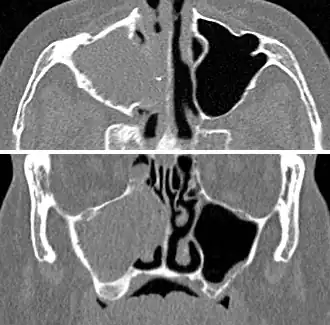

Imaging by either X-ray, CT, or MRI is generally not recommended unless complications develop.[66] Pain caused by sinusitis is sometimes confused for pain caused by pulpitis (toothache) of the maxillary teeth, and vice versa. Classically, the increased pain when tilting the head forwards separates sinusitis from pulpitis.[68]

For cases of maxillary sinusitis, limited field CBCT imaging, as compared to periapical radiographs, improves the ability to detect the teeth as the sources for sinusitis. A coronal CT picture may also be useful.[60]

Chronic

For sinusitis lasting more than 12 weeks, a CT scan is recommended.[66] On a CT scan, acute sinus secretions have a radiodensity of 10 to 25 Hounsfield units (HU). In a more chronic state, they become more viscous, with a radiodensity of 30 to 60 HU.[69]